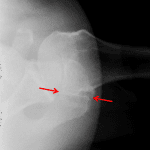

- No acute fracture or malalignment

- Mild degenerative changes of the glenohumeral and acromioclavicular joints with an inferior ossific protrusion from the glenoid

- Os acromiale

- Normal, Os acromiale

No acute fracture or malalignment.

Mild degenerative changes of the glenohumeral and acromioclavicular joints with an inferior ossific protrusion from the glenoid, which may represent an osteophyte or chronic Bankart lesion.

Os acromiale, normal variant.